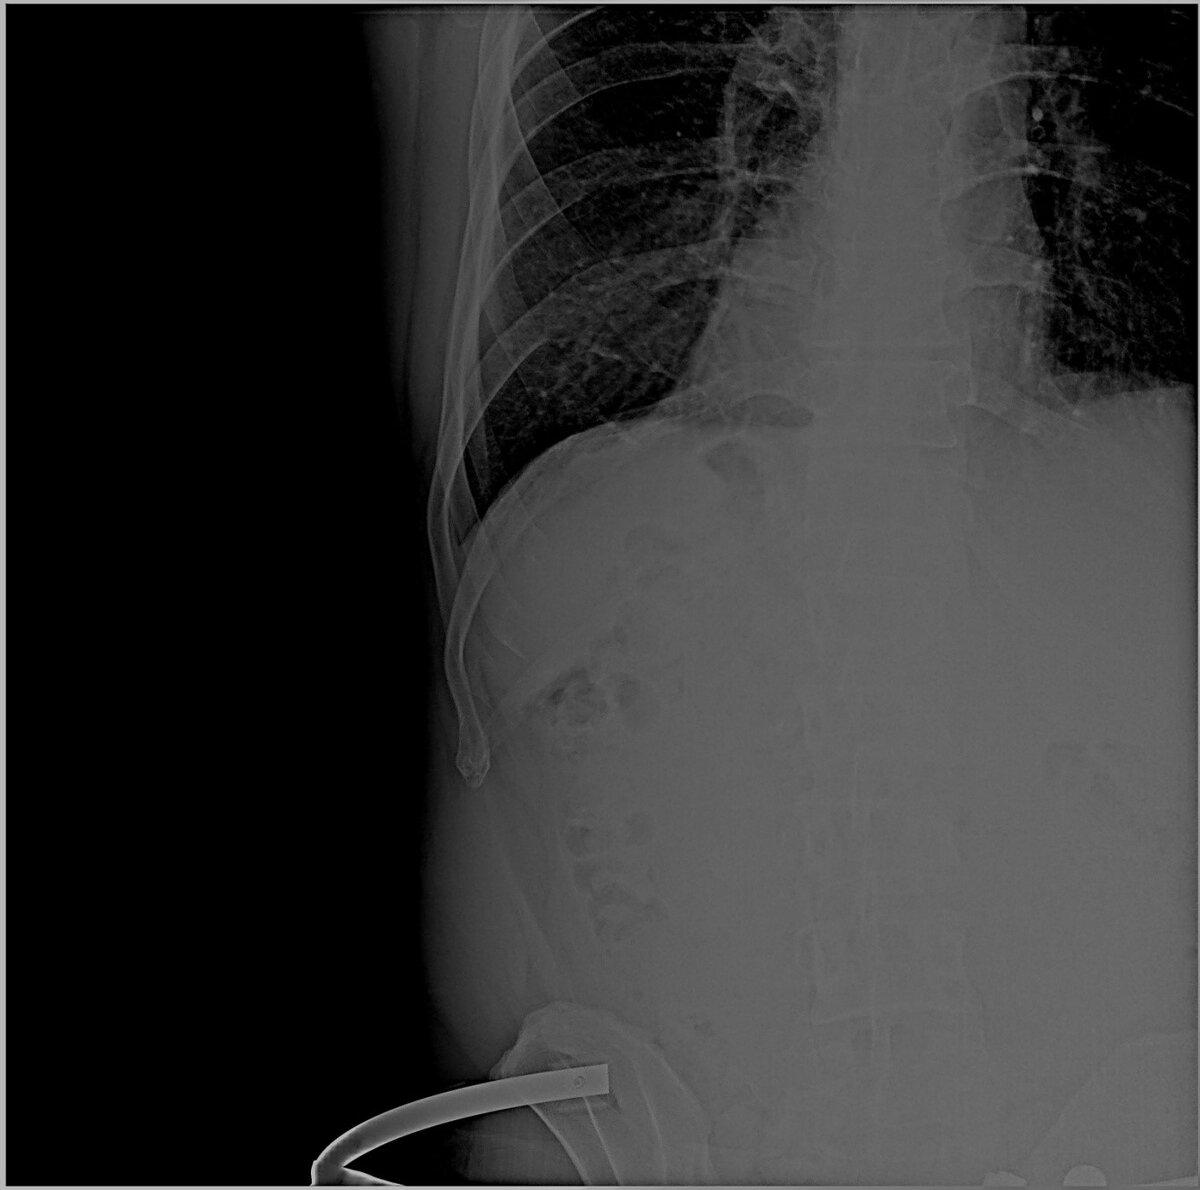

Здравствуйте. 14 февраля в результате падения после прыжка на лыжах, сильный удар левой стороной. Перелом 9 ребра в двух местах, ушибы. В травме сделали рентген и УЗИ. Говорят, по УЗИ всё нормально. ЧСС до травмы в покое была 58-62. Сейчас ниже 77 не опускается. Сижу - 85. Хожу -100-110. Во сне - 68-75 (до травмы - 52-54). Нормально ли это?  Не мог ли повредить селезёнку или ещё что, а на УЗИ не разглядели сразу?...

Здравствуйте. Перелом ребер сбоку и спереди и множество ушибов переносится нелегко, с нарушением дыхания, повышением ЧСС и переменами в АД. Дыхание может быть поверхностным, а пульс – учащенным в связи с возможным ушибом (сотрясением) сердца.

Необходимо провести электрокардиографический анализ на наличие такого нарушения, как экстрасистолия, желудочковая тахикардия, мерцательная аритмия, трепетание предсердий, пароксизмальная тахикардия или фибрилляция желудочков. На ЭКГ могут выявить изменения ST-T, перикардит, снижение в амплитуде зубца R и патологию в зубцах Q.

Падение и сильный удар левой стороной  негативно воздействует на различные зоны сердечной мышцы:

• миокард и проводящие пути, что нарушает метаболизм внутри миокарда;

• клапаны – возможен отек легких и острая клапанная недостаточность;

• коронарные артерии, что приводит к отслойке интимы или тромбозу, а позднее – к инфаркту миокарда.

Сердечные боли проявляются не сразу, через 1-2-3 суток, но учащенное  сердцебиение появляется сразу, может отдавать звоном в ушах. При нарушении  малого круга кровообращения возникает одышка и частое поверхностное дыхание.

Что касается повреждения других внутренних органов, в частности селезенки, то нужно сделать повторный снимок КТ или МРТ или УЗИ. Медлить нельзя, если удар был сильный и самочувствие плохое. Будьте здоровы!